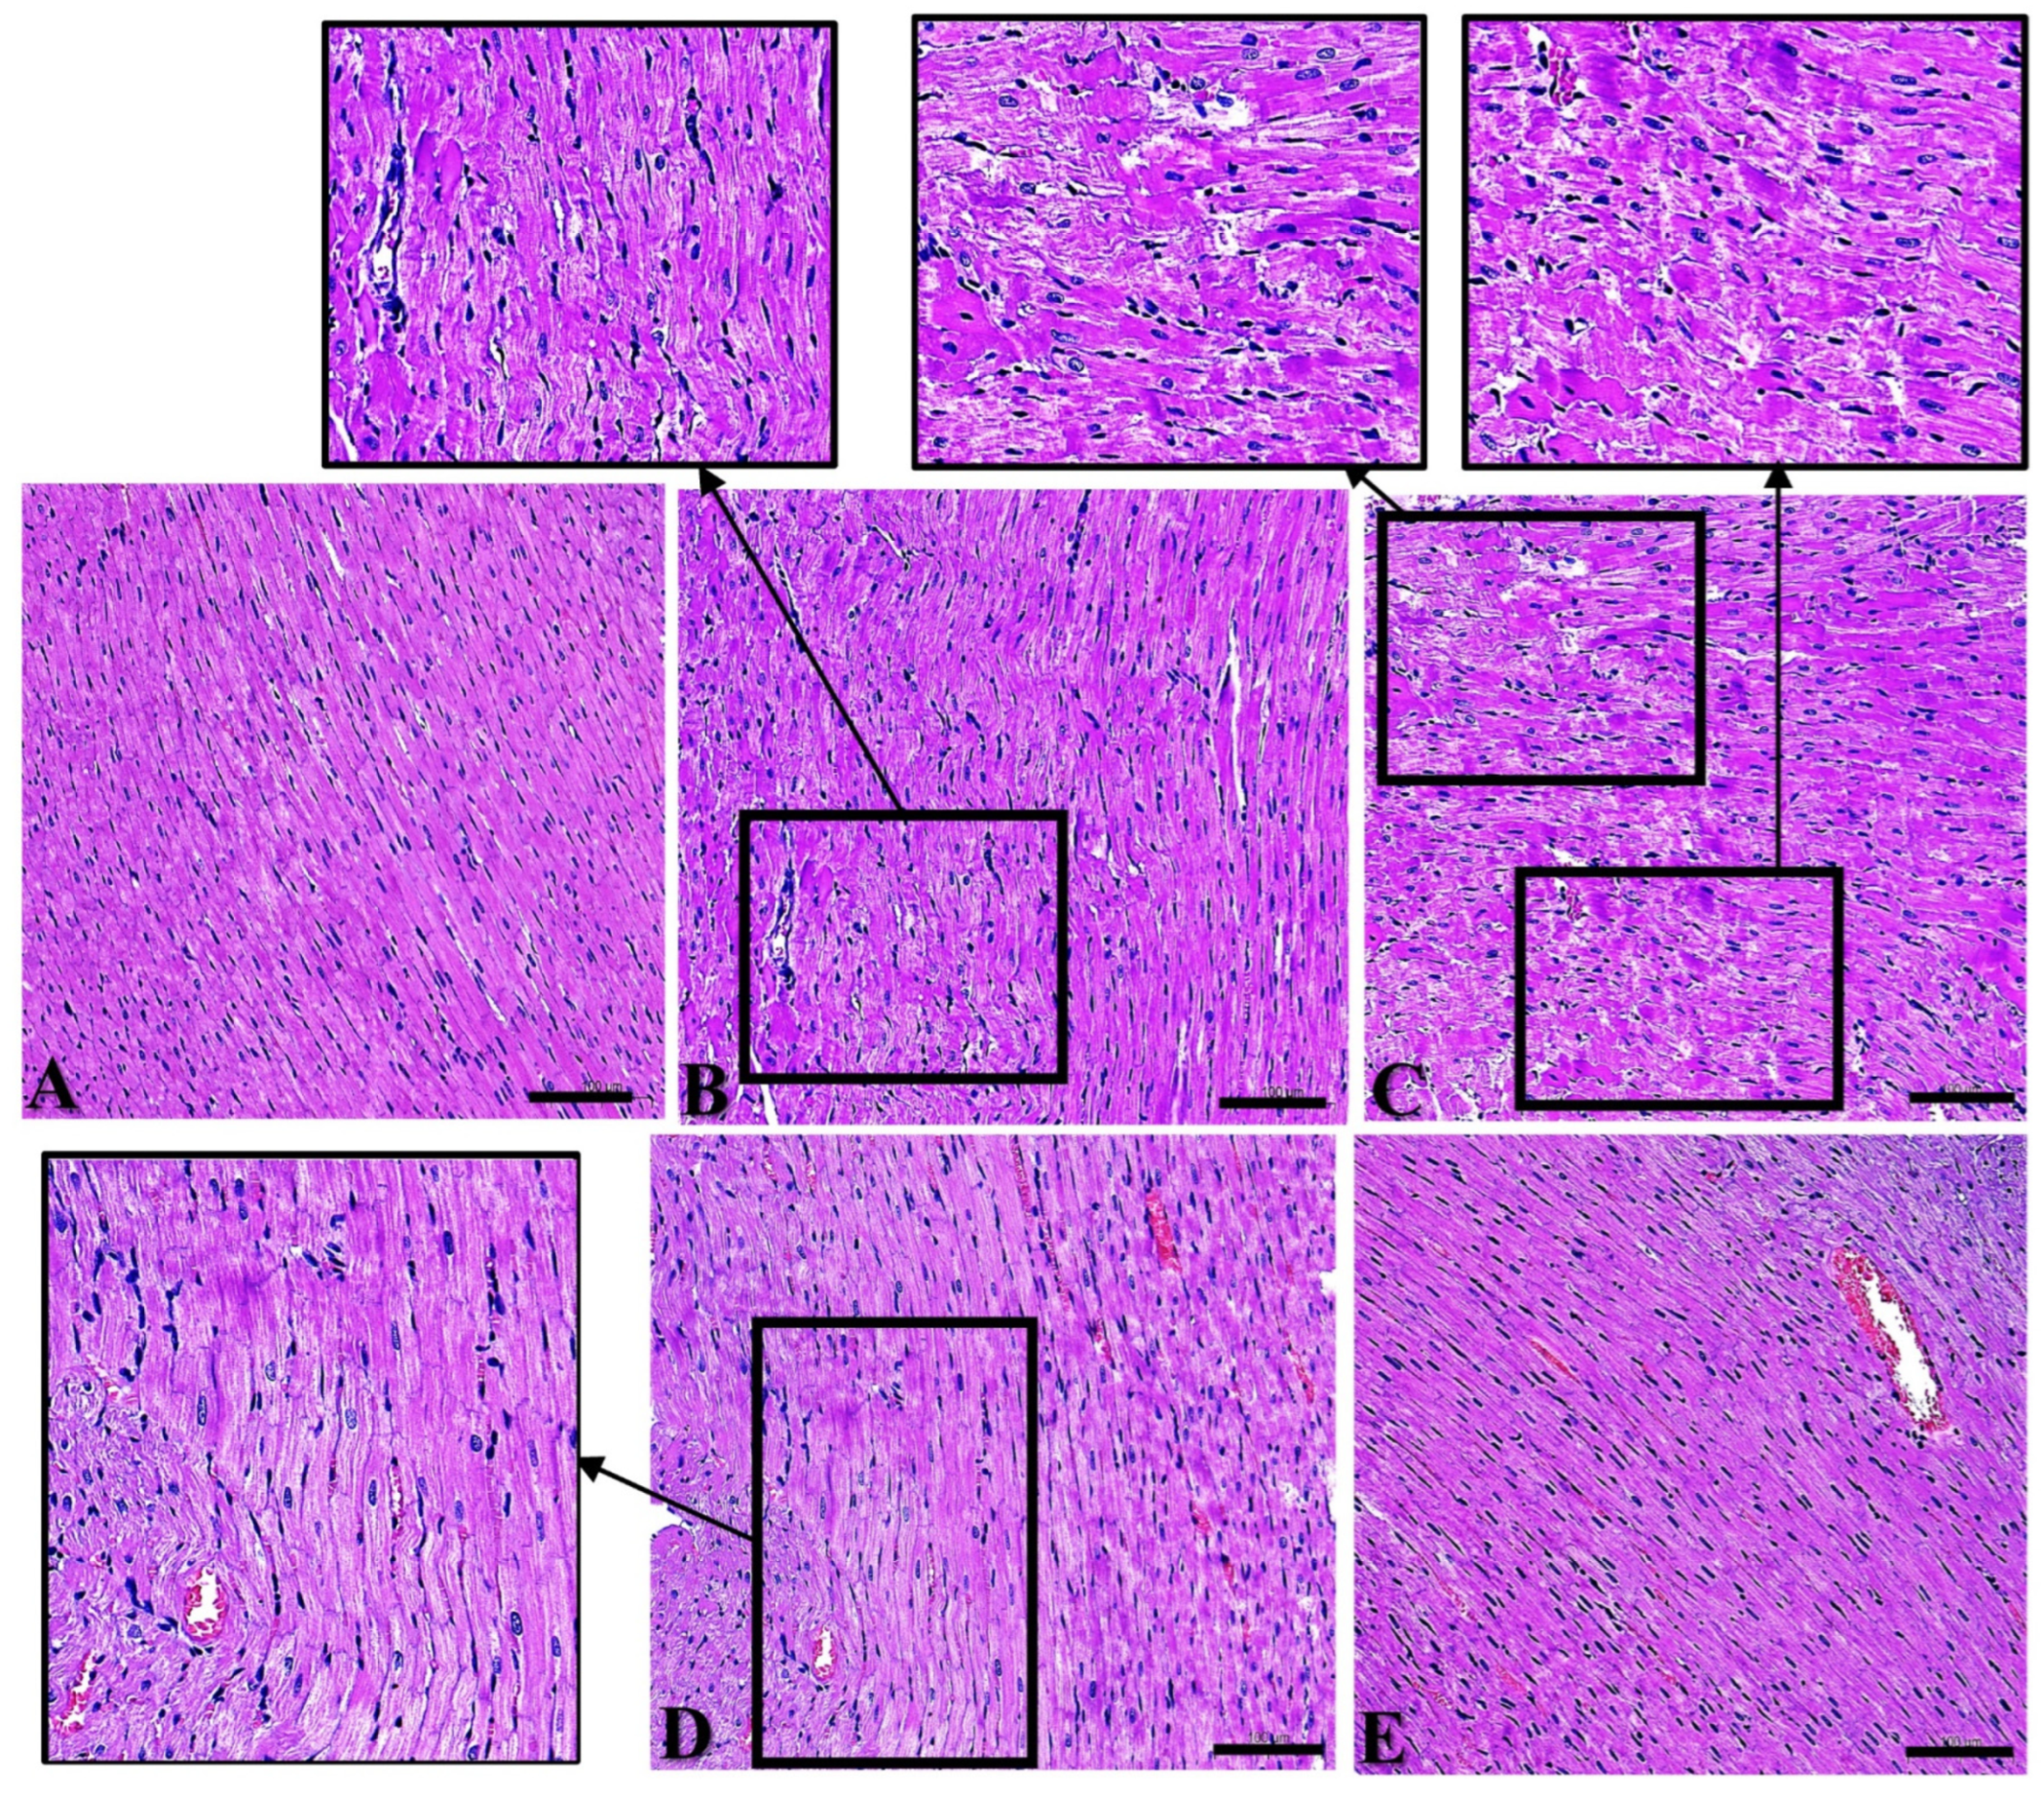

In this study, Days 1, 7, 14, and 28 after exposure were set for dynamic observation of the myocardial structure, with the intent being to explore the law of temporal change after radiation. Within 28 d after exposure, cardiac muscle fibers in Group C were closely and neatly arranged, with rare myocardial fibrosis and rupture, and the nuclei were regular in shape with rare pyknosis and hyperchromia (Figure 1A). On Day 1 after radiation, myocardial fibers in Group R were disordered and wavy, with irregular nuclei, pyknosis, and hyperchromasia (Figure 1B); on Day 7 after radiation, cardiac muscle fibers were disorganized, dissolved, fractured, and loosely arranged (Figure 1C); on Day 14 after radiation, myocardial fibers were more closely arranged than on Days 1 and 7 after radiation, and there were still a few wavy myocardial fibers (Figure 1D); on Day 28 after radiation, myocardial fibers were arranged tidily and tightly, and the damage was basically restored (Figure 1E). The above results clarified that the most significant time points of structural damage in this model were on Days 1 and 7. A recovery trend appeared on Day 14 and damage had largely recovered by Day 28.

Figure 1. Structural changes to rat’s myocardium after S-band exposure. (A) Group C; (B) Group R on Day 1; (C) Group R on Day 7; (D) Group R on Day 14; (E) Group R on Day 28. (AE) ×400, scale bar = 100 μm (black frames indicate wavy myocardial fibers and damaged areas).